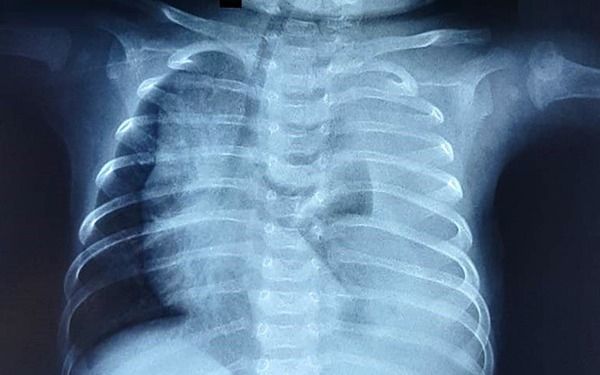

Bệnh màng trong là một loại bệnh lý thường xảy ra ở nhóm trẻ sinh non. Đây là một trong những nguyên nhân hàng đầu gây tử vong ở trẻ sơ sinh. Bài viết này sẽ giúp bạn hiểu rõ hơn về các nguyên nhân, triệu chứng và phương pháp điều trị bệnh màng trong ở trẻ sơ sinh.

Nguyên nhân chính của bệnh màng trong là do sự phát triển chưa hoàn chỉnh của đường hô hấp và thiếu hụt surfactant. Surfactant là một chất quan trọng trên bề mặt bên trong của túi phế nang, giúp duy trì sức căng bề mặt của phổi. Ở những thai nhi khỏe mạnh, surfactant bắt đầu tiết từ tuần thai thứ 20 và hoàn tất vào tuần thai thứ 32. Tuy nhiên, trẻ sinh non, đặc biệt là trẻ sinh trước 28 tuần, thường thiếu hụt surfactant, dẫn đến xẹp phổi và gây rối loạn hô hấp.

Bệnh màng trong ở trẻ sơ sinh thường biểu hiện với tình trạng suy hô hấp cấp tính sau khi sinh. Các triệu chứng thường khởi phát trong vòng 6 giờ đầu sau khi sinh. Các triệu chứng chính bao gồm: